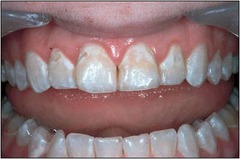

Meth mouth

-generalized extensive destruction of tooth surface -meth use